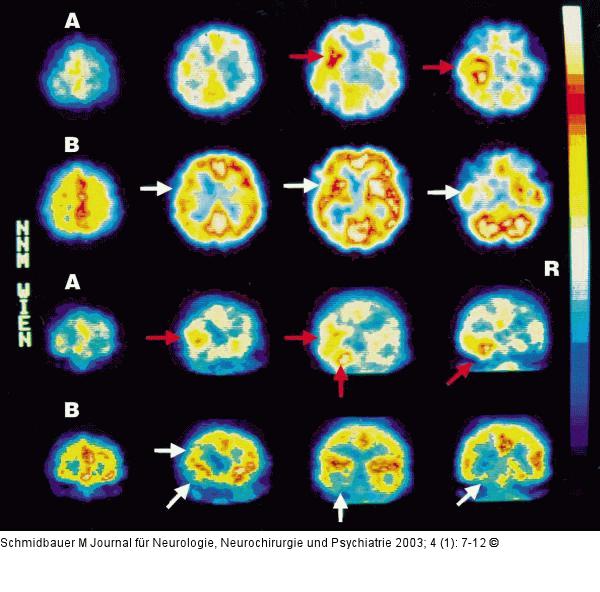

Abbildung 11: Temorallappenenzephalitis - Läsionen Dynamische Analyse der Läsionsentwicklung bei Temporallappenenzephalitis durch HSV. HMPAO-SPECT |

Dynamische Analyse der Läsionsentwicklung bei Temporallappenenzephalitis durch HSV. HMPAO-SPECT |